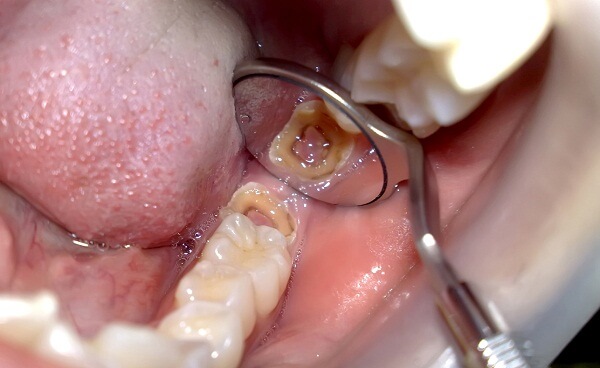

Thường chúng ta sẽ thấy đau và thấy một lỗ hổng màu đen trên răng mới phát hiện ra sâu răng. Nhưng thực chất, triệu chứng bắt đầu khi răng hình thành những đốm trắng. Sau đó mới tạo ra lỗ bám trên răng, lỗ đen này mới bắt đầu lan rộng dần dần. Lúc này, cơn đau buốt mới bắt đầu xuất hiện và răng trở nên nhạy cảm hơn khi ăn đồ nóng hoặc lạnh.

Thời gian chuyển từ đốm trắng sang lỗ màu đen trên răng nhanh hay chậm. Là tùy theo sức khỏe răng miệng và cách vệ sinh răng miệng của mỗi người.

Bọc sứ răng sâu là kỹ thuật mà bác sĩ sẽ thực hiện mài cùi chiếc răng bị sâu. Theo tỉ lệ được tính toán trước. Sau đó chụp mão sứ lên trên và gắn chặt lại. So với hàn trám răng, bọc sứ răng sâu với nhiều ưu đãi đang là giải pháp nha khoa được rất nhiều người tin tưởng sử dụng.